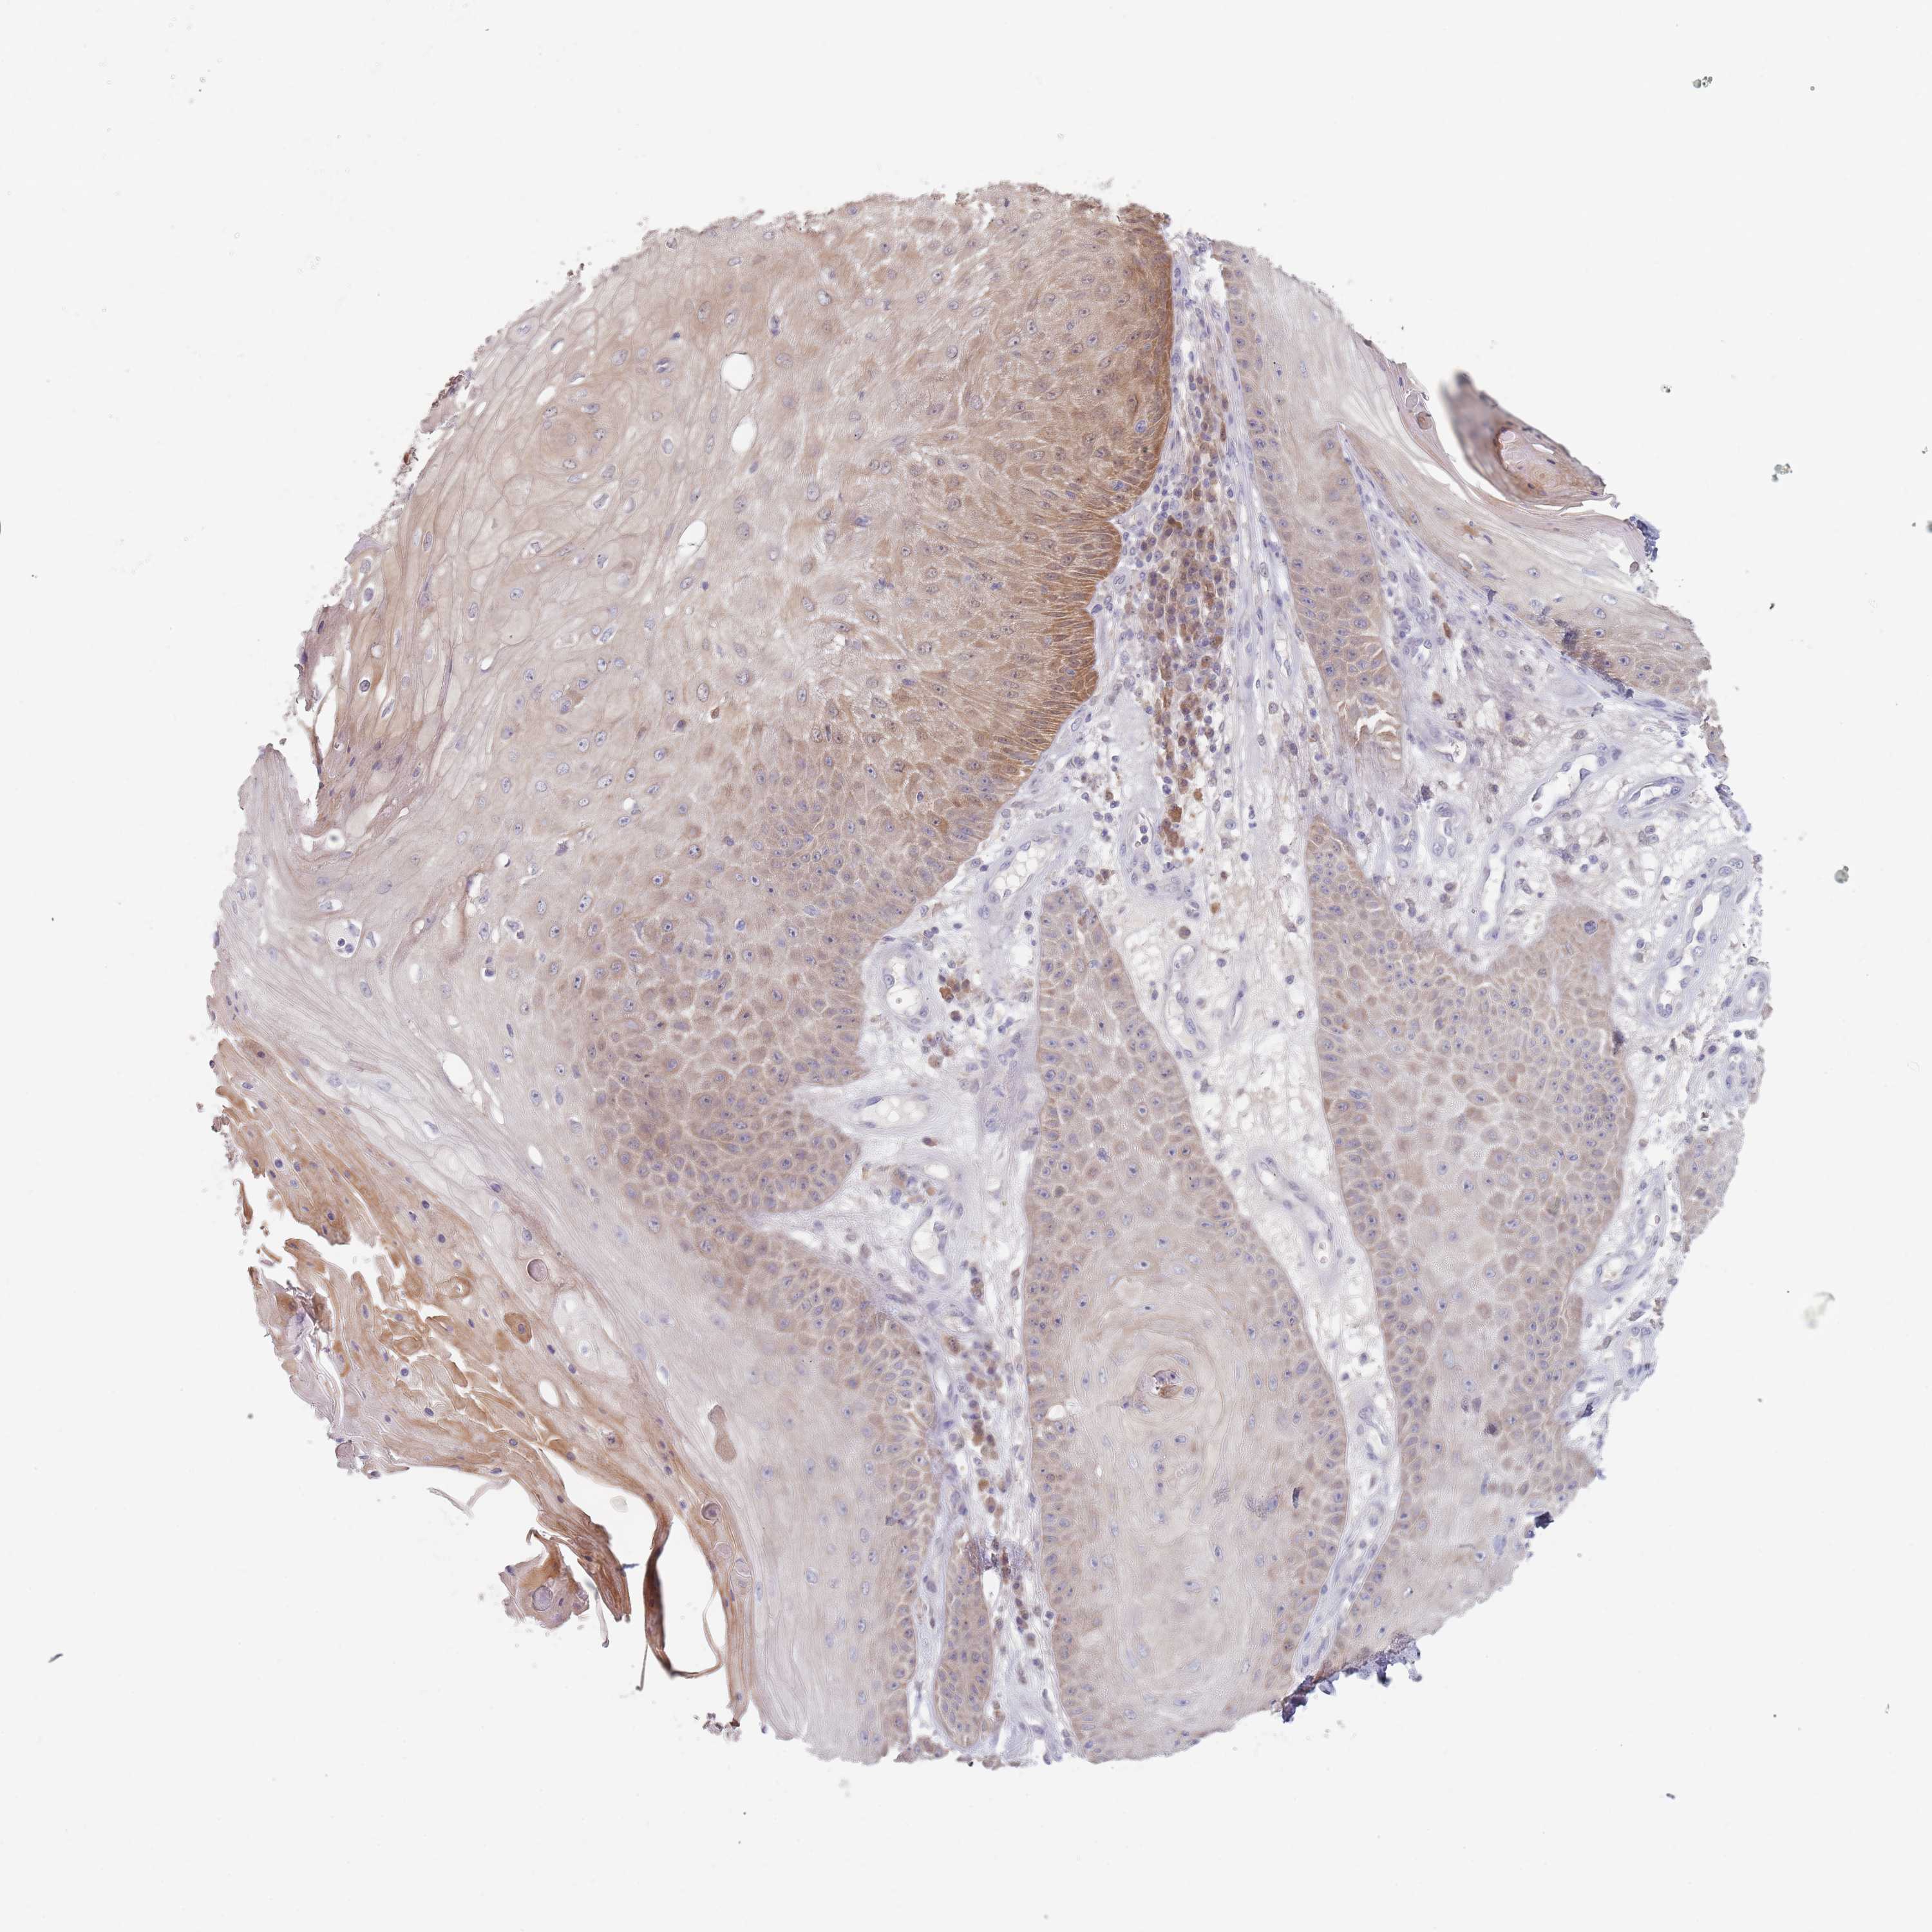

Basal cell and squamous cell cancer

SKIN CANCER - Protein expressioni

A mouse-over function shows sample information and annotation data. Click on an image to view it in a full screen mode. Samples can be filtered based on level of antibody staining by selecting one or several of the following categories: high, medium, low and not detected. The assay and annotation is described here.

Each image is clickable and will lead to virtual microscopy that enables deeper exploration of all samples and also displays staining intensity scores, fraction scores and subcellular localization as well as patient and tissue information for each sample.

Antibody HPA043766

Basal cell carcinoma